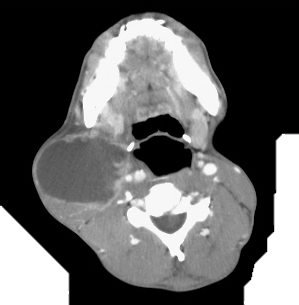

Definition: An acute bacterial infection (also known as “flesh eating bacteria”) that is characterized by necrosis of the deep fascia and subcutaneous tissues. It is a progressive and rapidly spreading infection in the deep tissue planes.

Aetiology: NF can be classified as polymicrobial (type I) or monomicrobial (type II), type I being more common. Type I NF is caused mainly by a combination of Group A Streptococcus (most common), Klebsiella, Clostridium, E. coli, Staphylococcus aureus, and Aeromonas hydrophila.

Clinical presentation: Pain, swelling and redness at the site of infection, followed by frank necrosis within days or weeks. Constitutional symptoms and signs such as fever, tachycardia and tachypnoea may be present. Presence of crepitus indicates gas produced by aerobic and anaerobic organisms is considered diagnostic of NF, but together with haemorrhagic bullae, skin necrosis, crepitus, sensory and motor deficits, it is a late sign of NF.

Epidemiology: Most common in immunocompromised hosts such as patients with HIV infection and diabetics.

Diagnosis: NF is a clinical diagnosis and Gram stain, blood and tissue cultures aid management.

Treatment: Surgical debridement, fasciotomy and broad spectrum intravenous antibiotics are the mainstay of treatment. Initial antibiotic treatment could include penicillin G and an aminoglycoside. Clindamycin may be added to cover streptococci, staphylococci, gram-negative bacilli, and anaerobes. Antibiotics are adjusted with culture results.

Complications: NF has a high mortality and other complications include necrotizing myositis, septic shock and multiple organ failure.